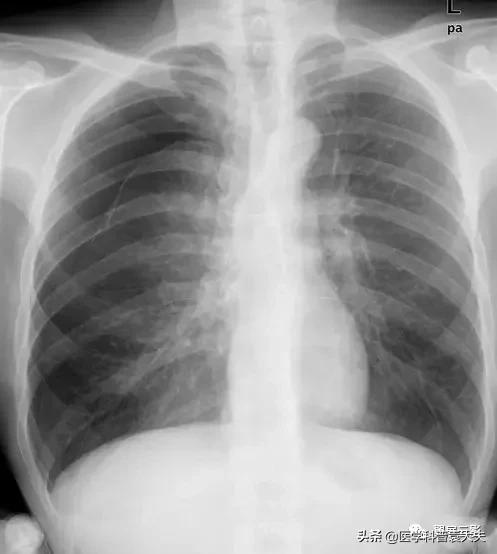

气胸时肺组织被压缩的程度,对于临床的治疗有着重要意义(如闭合性气胸,肺压缩<20%者,单纯卧床休闲气胸即可自行吸收),所以对气胸程度进行判定是必要的,可采用kircher方法计算,具体方法如下:

在气胸侧,以横突外缘至胸壁内缘为基准范围(为整个一侧肺野),

当肺野外侧受压至上述范围之1/4时,肺组织大约受压35%;

当受压至1/3时,肺组织受压50%;当受压1/2时,肺组织受压65%;

当受压至2/3时,肺组织受压80%;

而当肺组织全部被压缩至肺门,呈软组织密度时,肺组织受压约为95%。

如果少量气胸仅限于上肺野,则将肺野外带自上而下分为三等份,然后以上述方法中受压1/4时的35%均分,大约为10%-15%。

书上说的方法不少,但实际工作中,一般将气胸分为四度,采用两种最简单的方法来估算:

一、四等分法

气胸线由外向内回缩至四分之一肺野时实际容积约减少50%,至1/2时已达75%以上。及至内1/4时,肺容积只有原来的1/16左右。就功能而言,已全部丧失。

二、考虑气体分布特点、结合肺萎陷程度将气胸分为四度。

1度:新月形气体位于肺尖和上肺野外带,肺尖部发线不低于锁骨上线。

2度:发线影位于肺野中外1/3 处。肺尖低于锁骨下缘。

3度:无肺纹区达1/3至2/3部分。

4度:超过3度,无肺纹区超过肺野2/3以上。